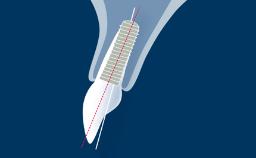

The understanding of the facial anatomy with its associated osseous and neurovascular structures is essential to the implant surgeon. During treatment planning and implant surgery, certain critical landmarks and boundaries must be respected. The anatomy of the maxilla and mandible is complex, and the implant surgeon should also keep in mind that many variations exist between individuals. The aim of this module is to review the basic anatomy of the facial region and to provide an overview of the important structures involved in implant dentistry in the average adult patient.

- describe the osseous structures of the mandible